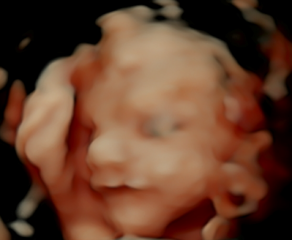

UPDATE: Today was the 5D ultrasound appointment.

My baby is a happy little boy! 💙

I also got a blue teddy bear with a little gadget inside that has a recording of his heartbeat. I hugged the teddy bear when I got home and listened to his heartbeat, and like a soppy sap, I cried. I still can't believe he's real.

I love your 3D pics, his little scrummy face. He's smiling! ☺️ Keep well!